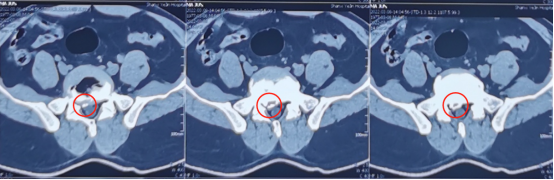

神经脊柱科熊东主任接诊吕先生后,尽快为他安排了各项检查,发现他的腿痛主要是从右侧臀部一直放射到小腿后侧,并且右侧直腿抬高呈阳性,双下肢皮肤浅感觉也出现了减退。根据吕先生拍的CT片子,可以发现腰5骶1椎间盘突出,并且已经严重压迫神经根,这种情况建议尽快进行手术解压。